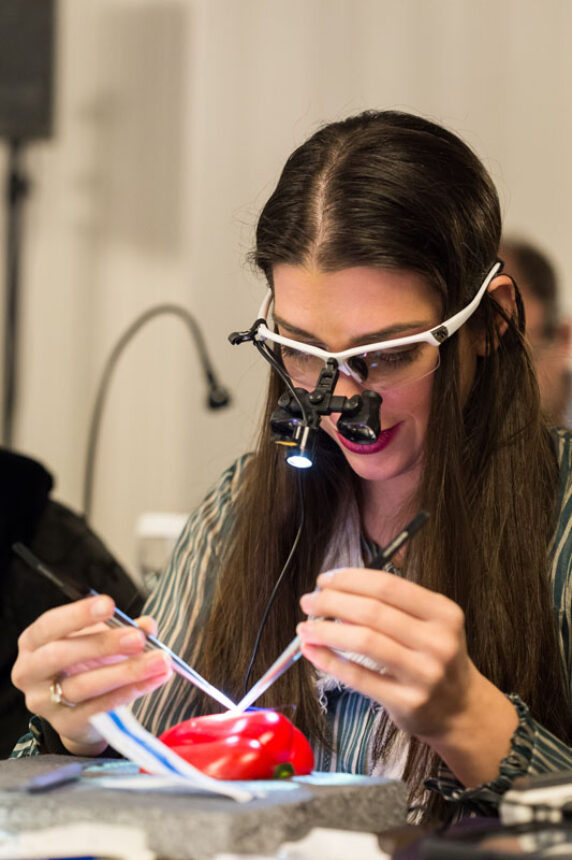

Suturing as a Key Indicator for Manual Skills (Hands on)

Mucosal Flap Preparation & Wound Stabilization (Hands on)

The Coronally Advanced Flap: Use of CTG for Root Coverage (Hands on)